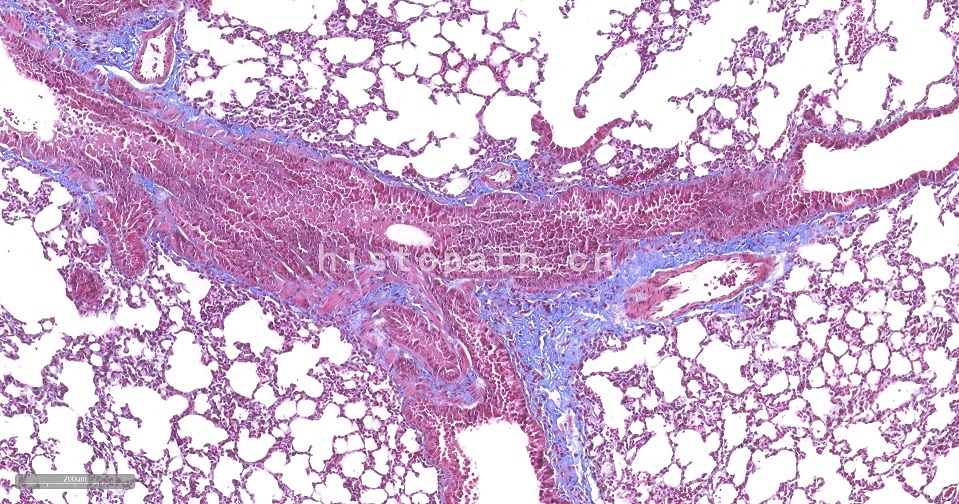

Masson染色

Masson染色原理:

Masson 三色染色又称马松染色,是结缔组织染色中最经典的一种方法,是胶原纤维染色权威而经典的技术方法。所谓三色染色通常是指染胞核和能选择性的显示胶原纤维和肌纤维。该法染色原理与阴离子染料分子的大小和组织的渗透有关:分子的大小由分子量来体现,小分子量易穿透结构致密、渗透性低的组织,而大分子量则只能进入结构疏松的、渗透性高的组织。然而,淡绿或苯胺蓝的分子量很大,因此 Masson 染色后肌纤维呈红色, 胶原纤维呈绿色或蓝色,主要用于区分胶原纤维和肌纤维。

染色结果:胶原纤维、黏液、软骨呈蓝色(如亮绿液染色为绿色),胞质、肌肉、纤维素、神经胶质呈红色,胞核黑蓝色。